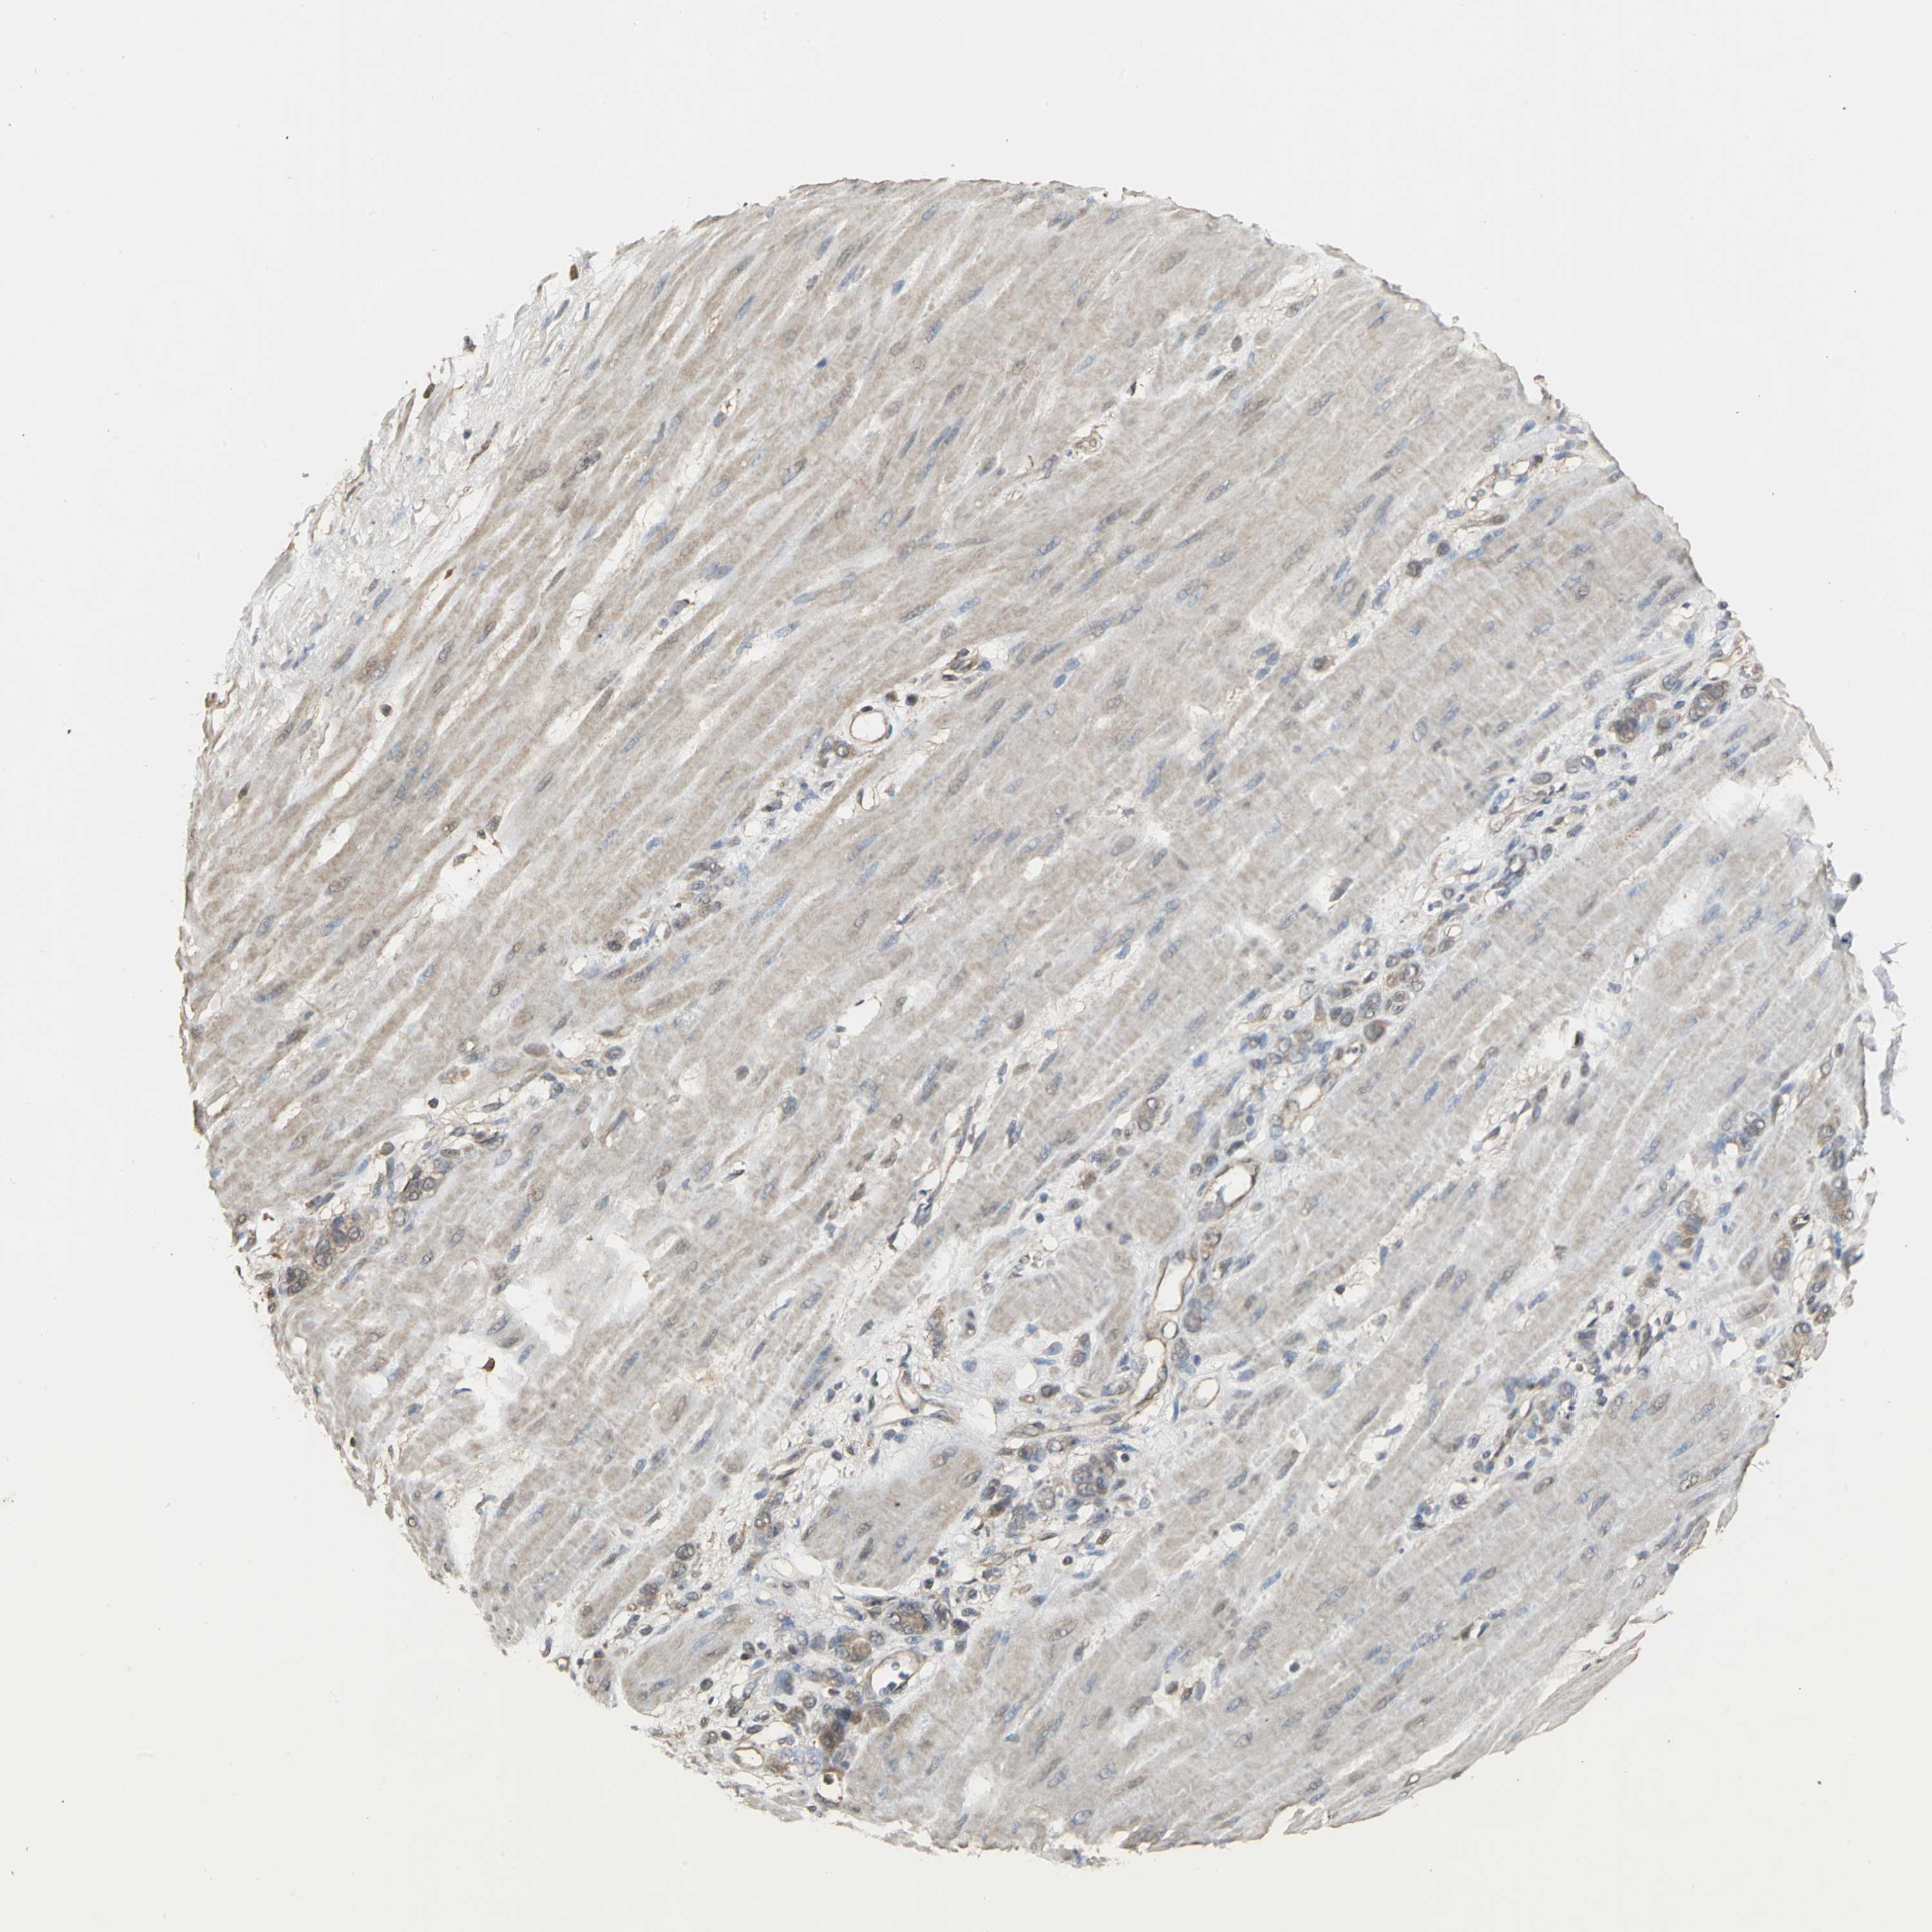

STOMACH CANCER - Protein expressioni

A mouse-over function shows sample information and annotation data. Click on an image to view it in a full screen mode. Samples can be filtered based on level of antibody staining by selecting one or several of the following categories: high, medium, low and not detected. The assay and annotation is described here.

Note that samples used for immunohistochemistry by the Human Protein Atlas do not correspond to samples in the TCGA dataset.

Antibody stainingi

Antibody staining in the annotated cell types in the current human tissue is reported as not detected, low, medium, or high, based on conventional immunohistochemistry profiling in selected tissues. This score is based on the combination of the staining intensity and fraction of stained cells.

Each image is clickable and will lead to virtual microscopy that enables deeper exploration of all samples and also displays staining intensity scores, fraction scores and subcellular localization as well as patient and tissue information for each sample.

Antibody HPA004190

Antibody CAB005870

Staining

High

Medium

Low

Not detected

Intensity

Strong

Moderate

Weak

Negative

Quantity

>75%

75%-25%

<25%

None

Location

Nuclear

Cytoplasmic/membranous

Cytoplasmic/membranous,nuclear

Adenocarcinoma, NOS

Adenocarcinoma, High grade